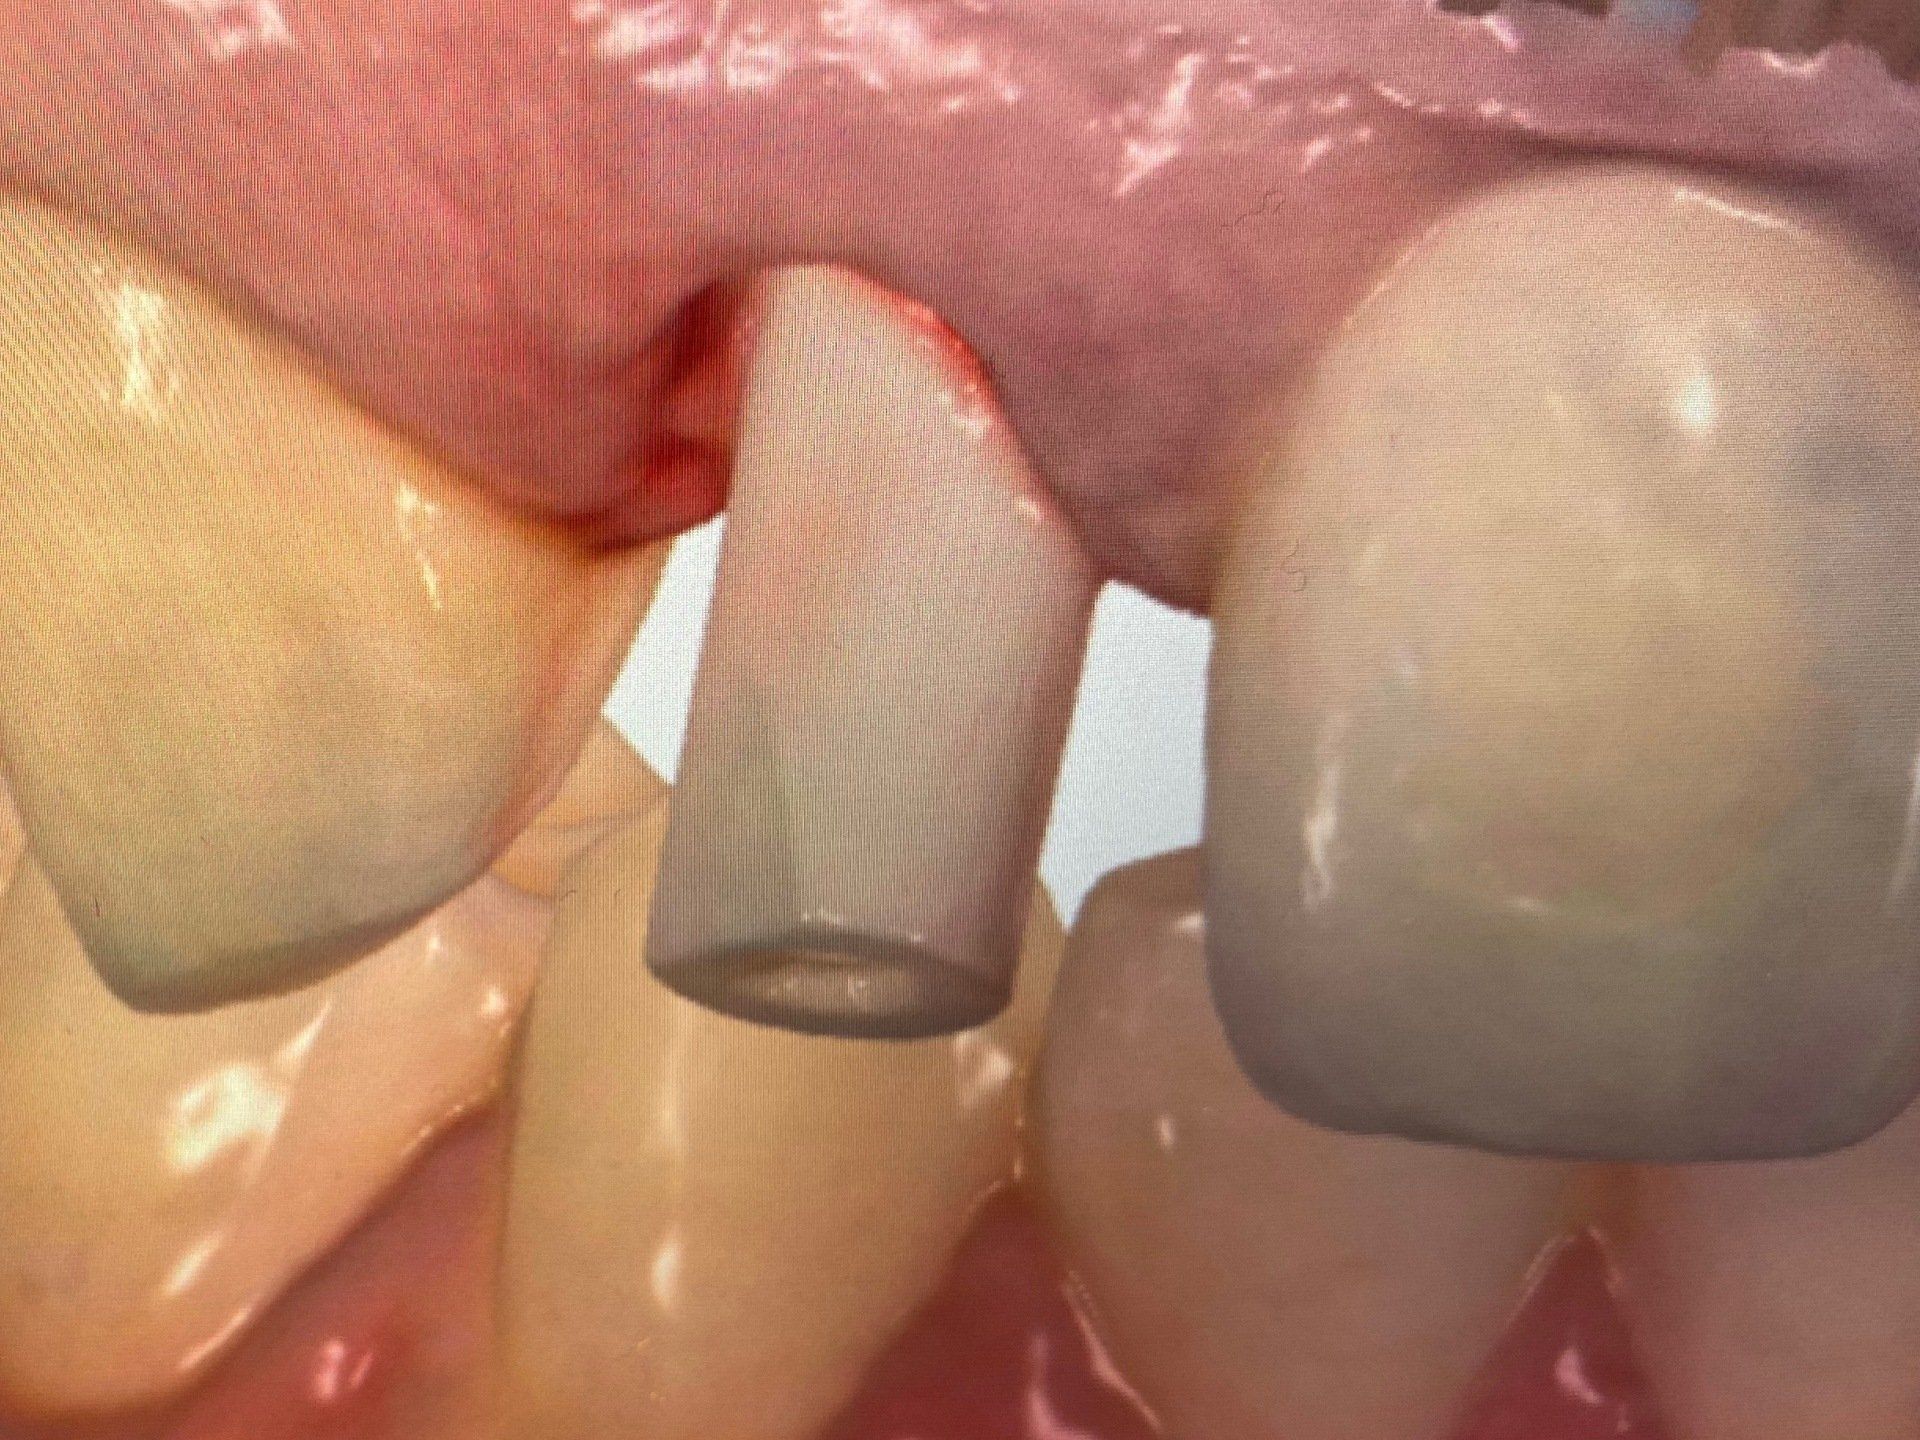

Intraoraler Scan:

Fall 1:

Intraoraler Scan mit Trios, Scanbody 12.